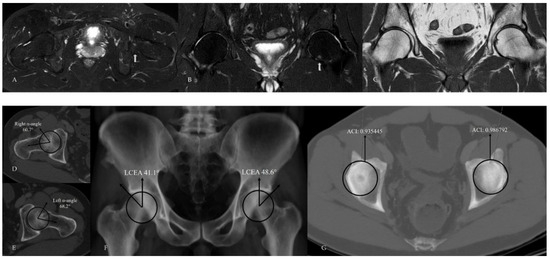

Figure 9.

Hip MRI demonstrates focal bone marrow edema in the inferior aspect of the left femoral head on (A) axial and (B) coronal fat-suppressed T2-weighted images (white arrow). (C) Coronal T1-weighted image shows no associated additional imaging findings. (D,E) CT demonstrates alpha angle measurements, and (F) LCEA measurements indicate bilateral mixed-type femoroacetabular impingement. (G) Acetabular overcoverage is confirmed using the ACI.